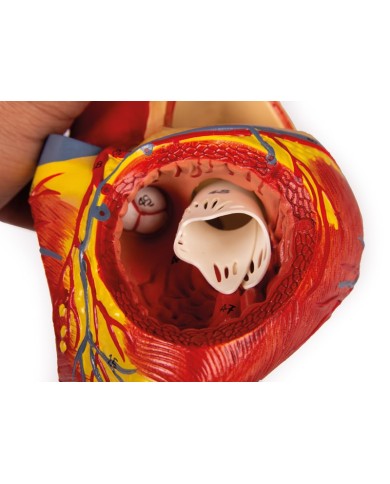

La parete anteriore del cuore è staccabile per poter vedere i ventricoli.